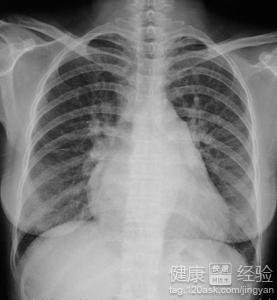

3後天性風濕性心髒病的診斷也並不是單一的,而是要結合一些臨床的病理反應和做心電圖,包括CT進行確診的,患有這種疾病的患者,一般來說會出現較多的惡心,咳嗽,以及平時生活中會有明顯的呼吸不暢或者困難,甚至有的會直接咳血,是比較嚴重的了